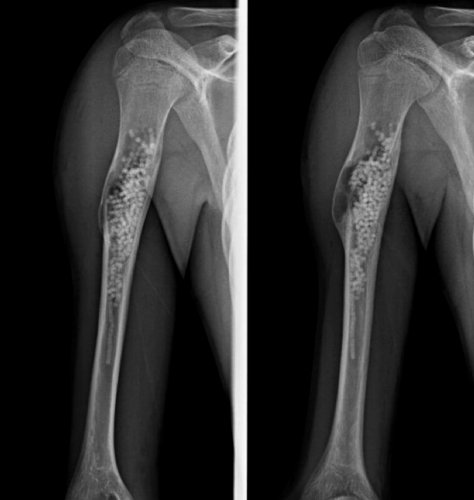

CISTI SOLITARIA DELL'OSSO TRATTATA CON PERLE DI TRISOLFATO CALCICO

Fig 1 Maschio 11 anni Cisti Omerale 1 mese post frattura patologica e pre trattamento